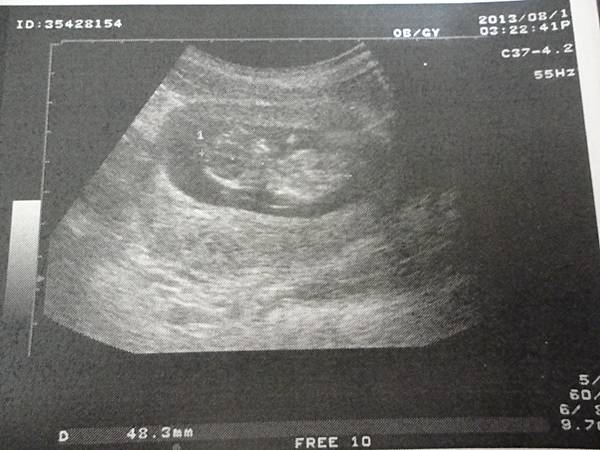

下面這張就比較有頭跟身體的FU啦XDDDDDD

那是11周4.8CM時拍的~~